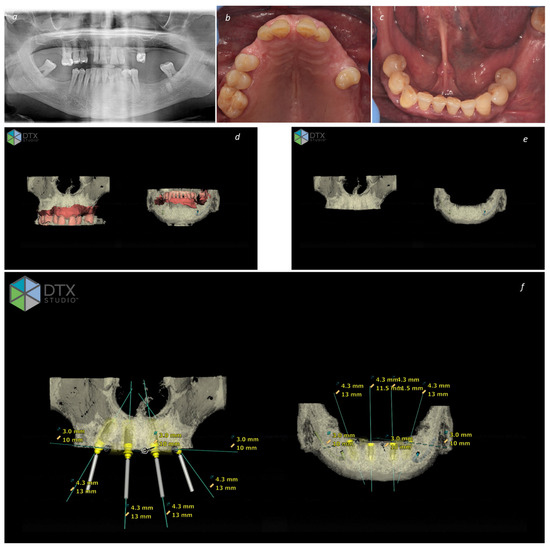

Figure 1.

Planning a full-arch bimaxillary rehabilitation through the All-on-4 Concept: (a) Pre-treatment orthopantomography; (b) Pre-treatment intraoral photograph of the maxilla; (c) pre-treatment intraoral photograph of the mandible; (d) DTX Studio image exhibiting the pre-treatment condition in the maxilla and mandible with superimposition of CBCT and Intraoral Scanner (smart fusion); (e) DTX Studio image of the planning exhibiting the bone regularization to achieve a stable platform for implant insertion in the maxilla and mandible; (f) DTX Studio image of the final planning exhibiting the implant planning (diameter and length) in the maxilla and mandible.